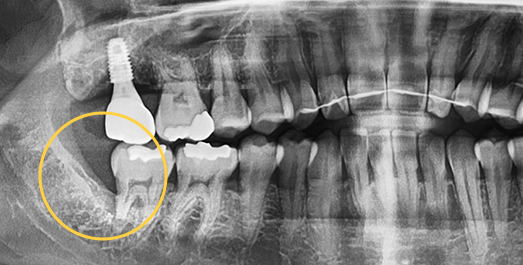

Even advanced cases

can be extracted.

With extensive experience in numerous advanced cases and a wide range of wisdom tooth extractions, you no longer need to go to a university hospital.

• BEFORE

• AFTER

Treatment Date : 2024.09.04

Treatment Date : 2023.12.22

Treatment Date : 2024.05.28